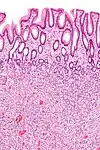

| Hyperplastic polyp of the stomach | Stomach | Elongated, tortuous, and cystic foveolae separated by edematous and inflamed stroma.[4] | ![]() |